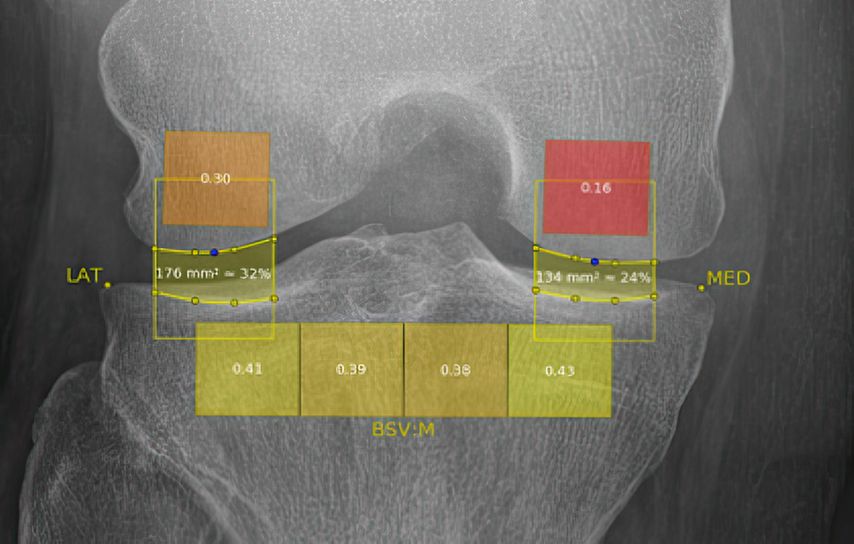

Dem Prozess der Degeneration des Gelenkknorpels, der mit der OA einhergeht, gehen subtile Veränderungen der trabekulären Knochenstruktur und die Bildung von neuem Knochen an den Gelenkrändern, den sogenannten Osteophyten, voraus. Es wurde nachgewiesen, dass Veränderungen der trabekulären Knochenstruktur im subchondralen Knochenkompartiment des Schienbeins bereits Monate bis Jahre vor den nachweisbaren Veränderungen der Gelenkknorpeldicke auftreten. Infolgedessen war der Zusammenhang der radiologischen OA-Progression und -Inzidenz mit der Analyse der trabekulären Struktur des Tibiakopfes im Fokus der Forschung. Die Mehrheit der Studien untersucht die mathematische fraktale Architektur der Knochentextur des subchondralen Teils des Tibiakopfes, die aus Röntgenaufnahmen gewonnen wird. Die Anwendung fraktaler Analysen für die Analyse der subchondralen Knochenmikroarchitektur basiert auf der Tatsache, dass die auf einfachen Röntgenaufnahmen erkennbare trabekuläre Knochentextur direkt mit der zugrunde liegenden dreidimensionalen trabekulären Knochenstruktur korreliert wurde. In dieser mathematischen digitalen Analyse ergibt sich ein sogenannter „bone structure value“ (BSV), der sich in KI(künstliche Intelligenz)-Algorithmen als Parameter der Prognose des Fortschreitens und Auftretens von OA trainieren lässt. Der BSV misst die fraktale Dimension der Knochentextur mittels Hurst-Koeffizient, der ein Maß für die weiträumige Abhängigkeit von Datenpunkten (Pixel) ist und damit ein Parameter der Entropie (Strukturregelmäßigkeit) des Gewebes, und zeigt damit früher Veränderungen der Mikrostruktur des Knochens an, die mit dem bloßen Auge nicht erkennbar sind.

Bedeutung von Veränderungen in der subchondralen Knochenstruktur

Unsere Ergebnisse deuten darauf hin, dass die computergestützte Auswertung digitaler Röntgendaten frühe Veränderungen in der subchondralen Knochenstruktur qualifiziert und quantifiziert und einige Rückschlüsse auf die OA-Entwicklung und -Prognose zulässt. Die prospektive Anwendung und Weiterverfolgung einer solchen Röntgenbeurteilung und einfach zu bedienenden Softwaretechnologie werden dazu beitragen, objektive Ergebnisse für OA-Studien zu schaffen und auch in der Patientenberatung besonders Patient:innen mit einem hohen Arthroseprogressionsrisiko intensiv zu beraten und zu behandeln.